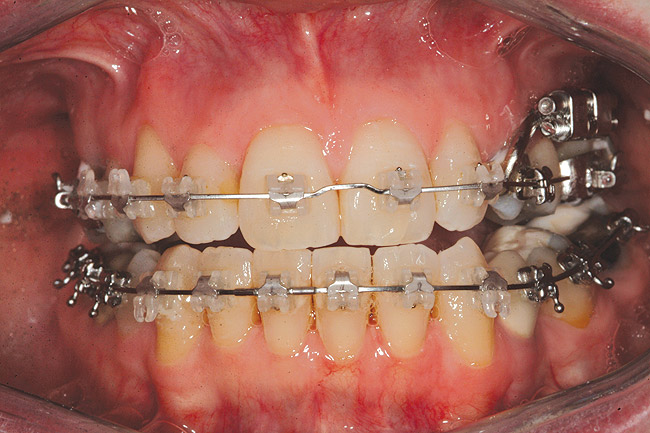

Fig 12 (and Fig 13). Incisors were too upright and had severe incisal wear. He was concerned about esthetics of the worn teeth and his insufficient lip support. Progress photo and panorex 9 months after corticotomies were performed on Nos. 6 through 11. Previous extraction sites were reopened orthodontically to improve function and fill lip support. Incisal edges were restored provisionally with composite resin. Note that despite the creation of adequate spaces to replace missing teeth, there is inadequate room for placement of dental implants because of severe tipping of all the anterior teeth. Osteotomy SFOT may have been a better choice because it would have allowed needed alveoloskeletal correction (without excessive tipping) instead of the primarily dentoalveolar correction common in corticotomy SFOT. Restorative dentist: Brad Jones, DDS.

Figure 12

Fig 13 (and Fig 12). Incisors were too upright and had severe incisal wear. He was concerned about esthetics of the worn teeth and his insufficient lip support. Progress photo and panorex 9 months after corticotomies were performed on Nos. 6 through 11.

Figure 13